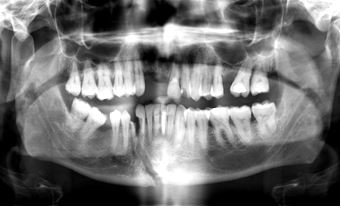

Background and aims: Treatment for maxillofacial fractures, which affect the mandible, maxilla, zygomatic bone, and nose, depends on the form and severity of the injury. In order to manage complicated patients needing closed reduction or open reduction and internal fixation, university hospitals such as Al-Thawra General Modern Hospital in Sana'a employ cutting-edge surgical procedures and interdisciplinary care. The purpose of this retrospective study was to evaluate related fracture types and aetiology, as well as the types and treatments of maxillofacial fractures among patients sent to the Al-Thawra General Modern Hospital in Sana'a.

Results: Males constituted 78.7% and females 21.3% of the population studied. Among children, males were 77.74% and females 22.26%, with a mean age of 10.4 years, primarily in the 11–15-year age group (56.1%). In adults, males made up 79.1% and females 20.9%, with a mean age of 26.1 years, predominantly aged 16–25 years (60.6%). The primary causes of fractures were road traffic accidents (56.1%), falls from heights (22.5%), and assaults (13.3%). In an alternate dataset, traffic accidents were noted at 50%. Mandible fractures were the most frequent, accounting for 31.4% of cases, followed by zygomatic (17.2%) and condylar fractures (8.9%).

Conclusions: The majority of victims of maxillofacial fractures and injuries in the child and adult categories were males between the ages of 16 and 25. Traffic accidents, falls from heights, and attacks were the main causes of fractures. Zygomatic and condylar fractures were the next most common, after mandibular fractures.